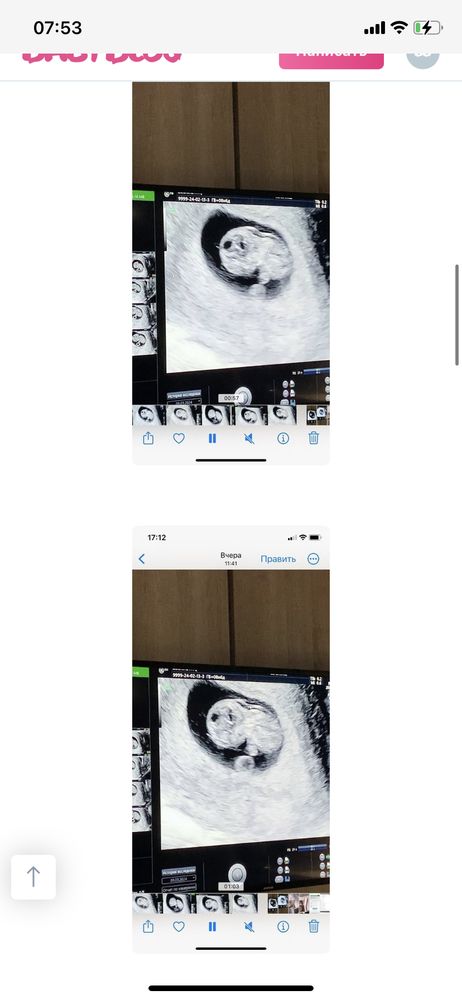

Девочки, доброе утро.. Приложу описание своей ситуации по узи в 9 -то неделек (первые пять фото). Ходила на узи в 9,5 недель (шестое фото) Всё таки есть расширение воротникового пространства? Хожу в платную клинику с самого начала беременности. Попросила её измерить все таки, она померила, но там, где маленькое воротниковое пространство и сказала 1,5, но можно было замерить в другом месте, где оно больше. Вроде в конце она померила большой замер и ничего не сказала мне, а я обратила на это внимание 😢 Я её спросила несколько раз, она сказала, что все хорошо, но мне кажется, что она меня так просто успокаивает..